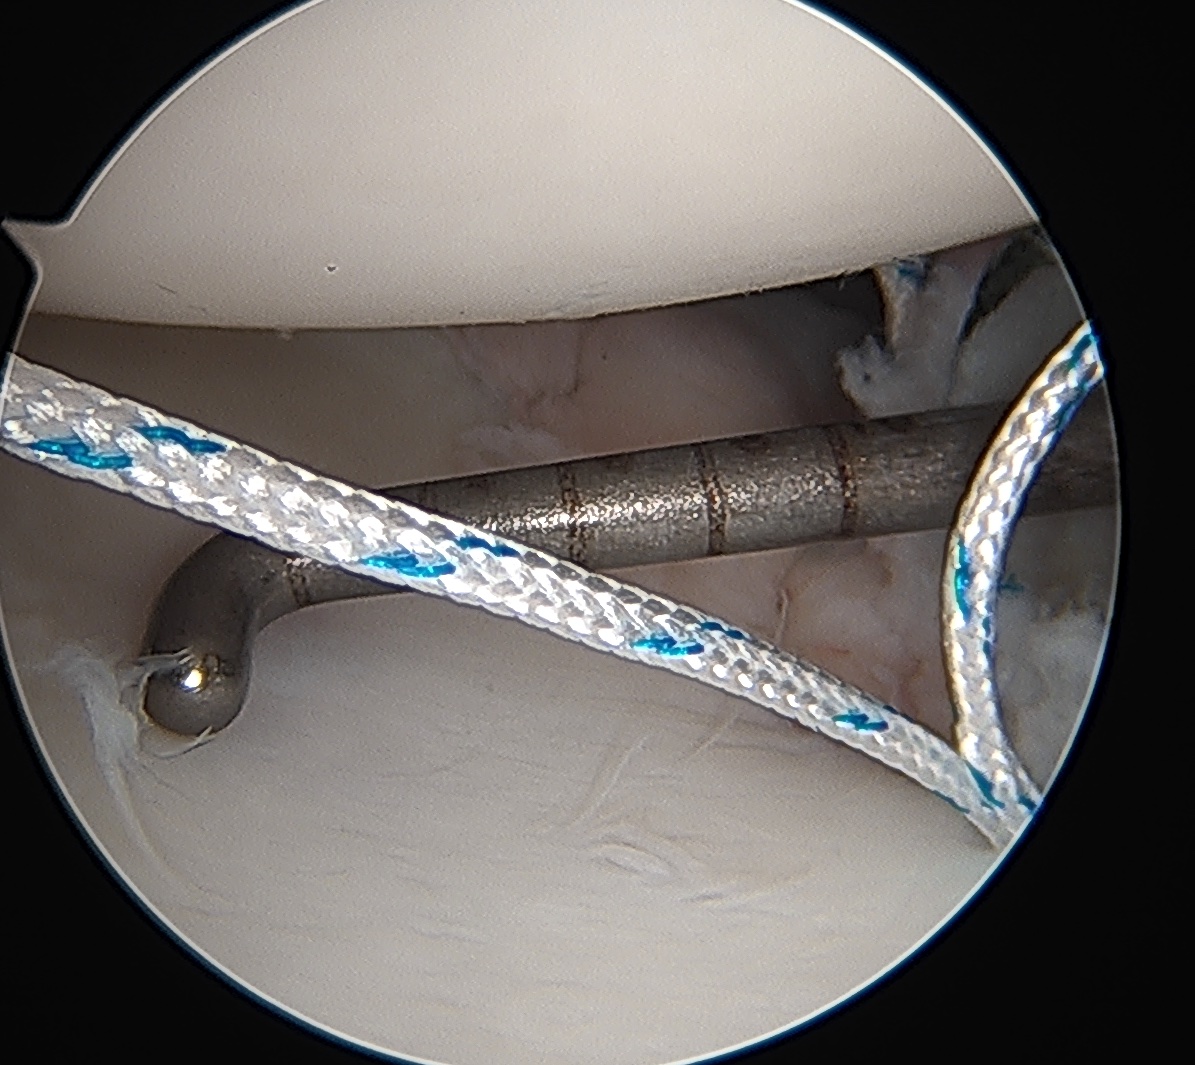

Posterior labral repair

Posterior capsular plication